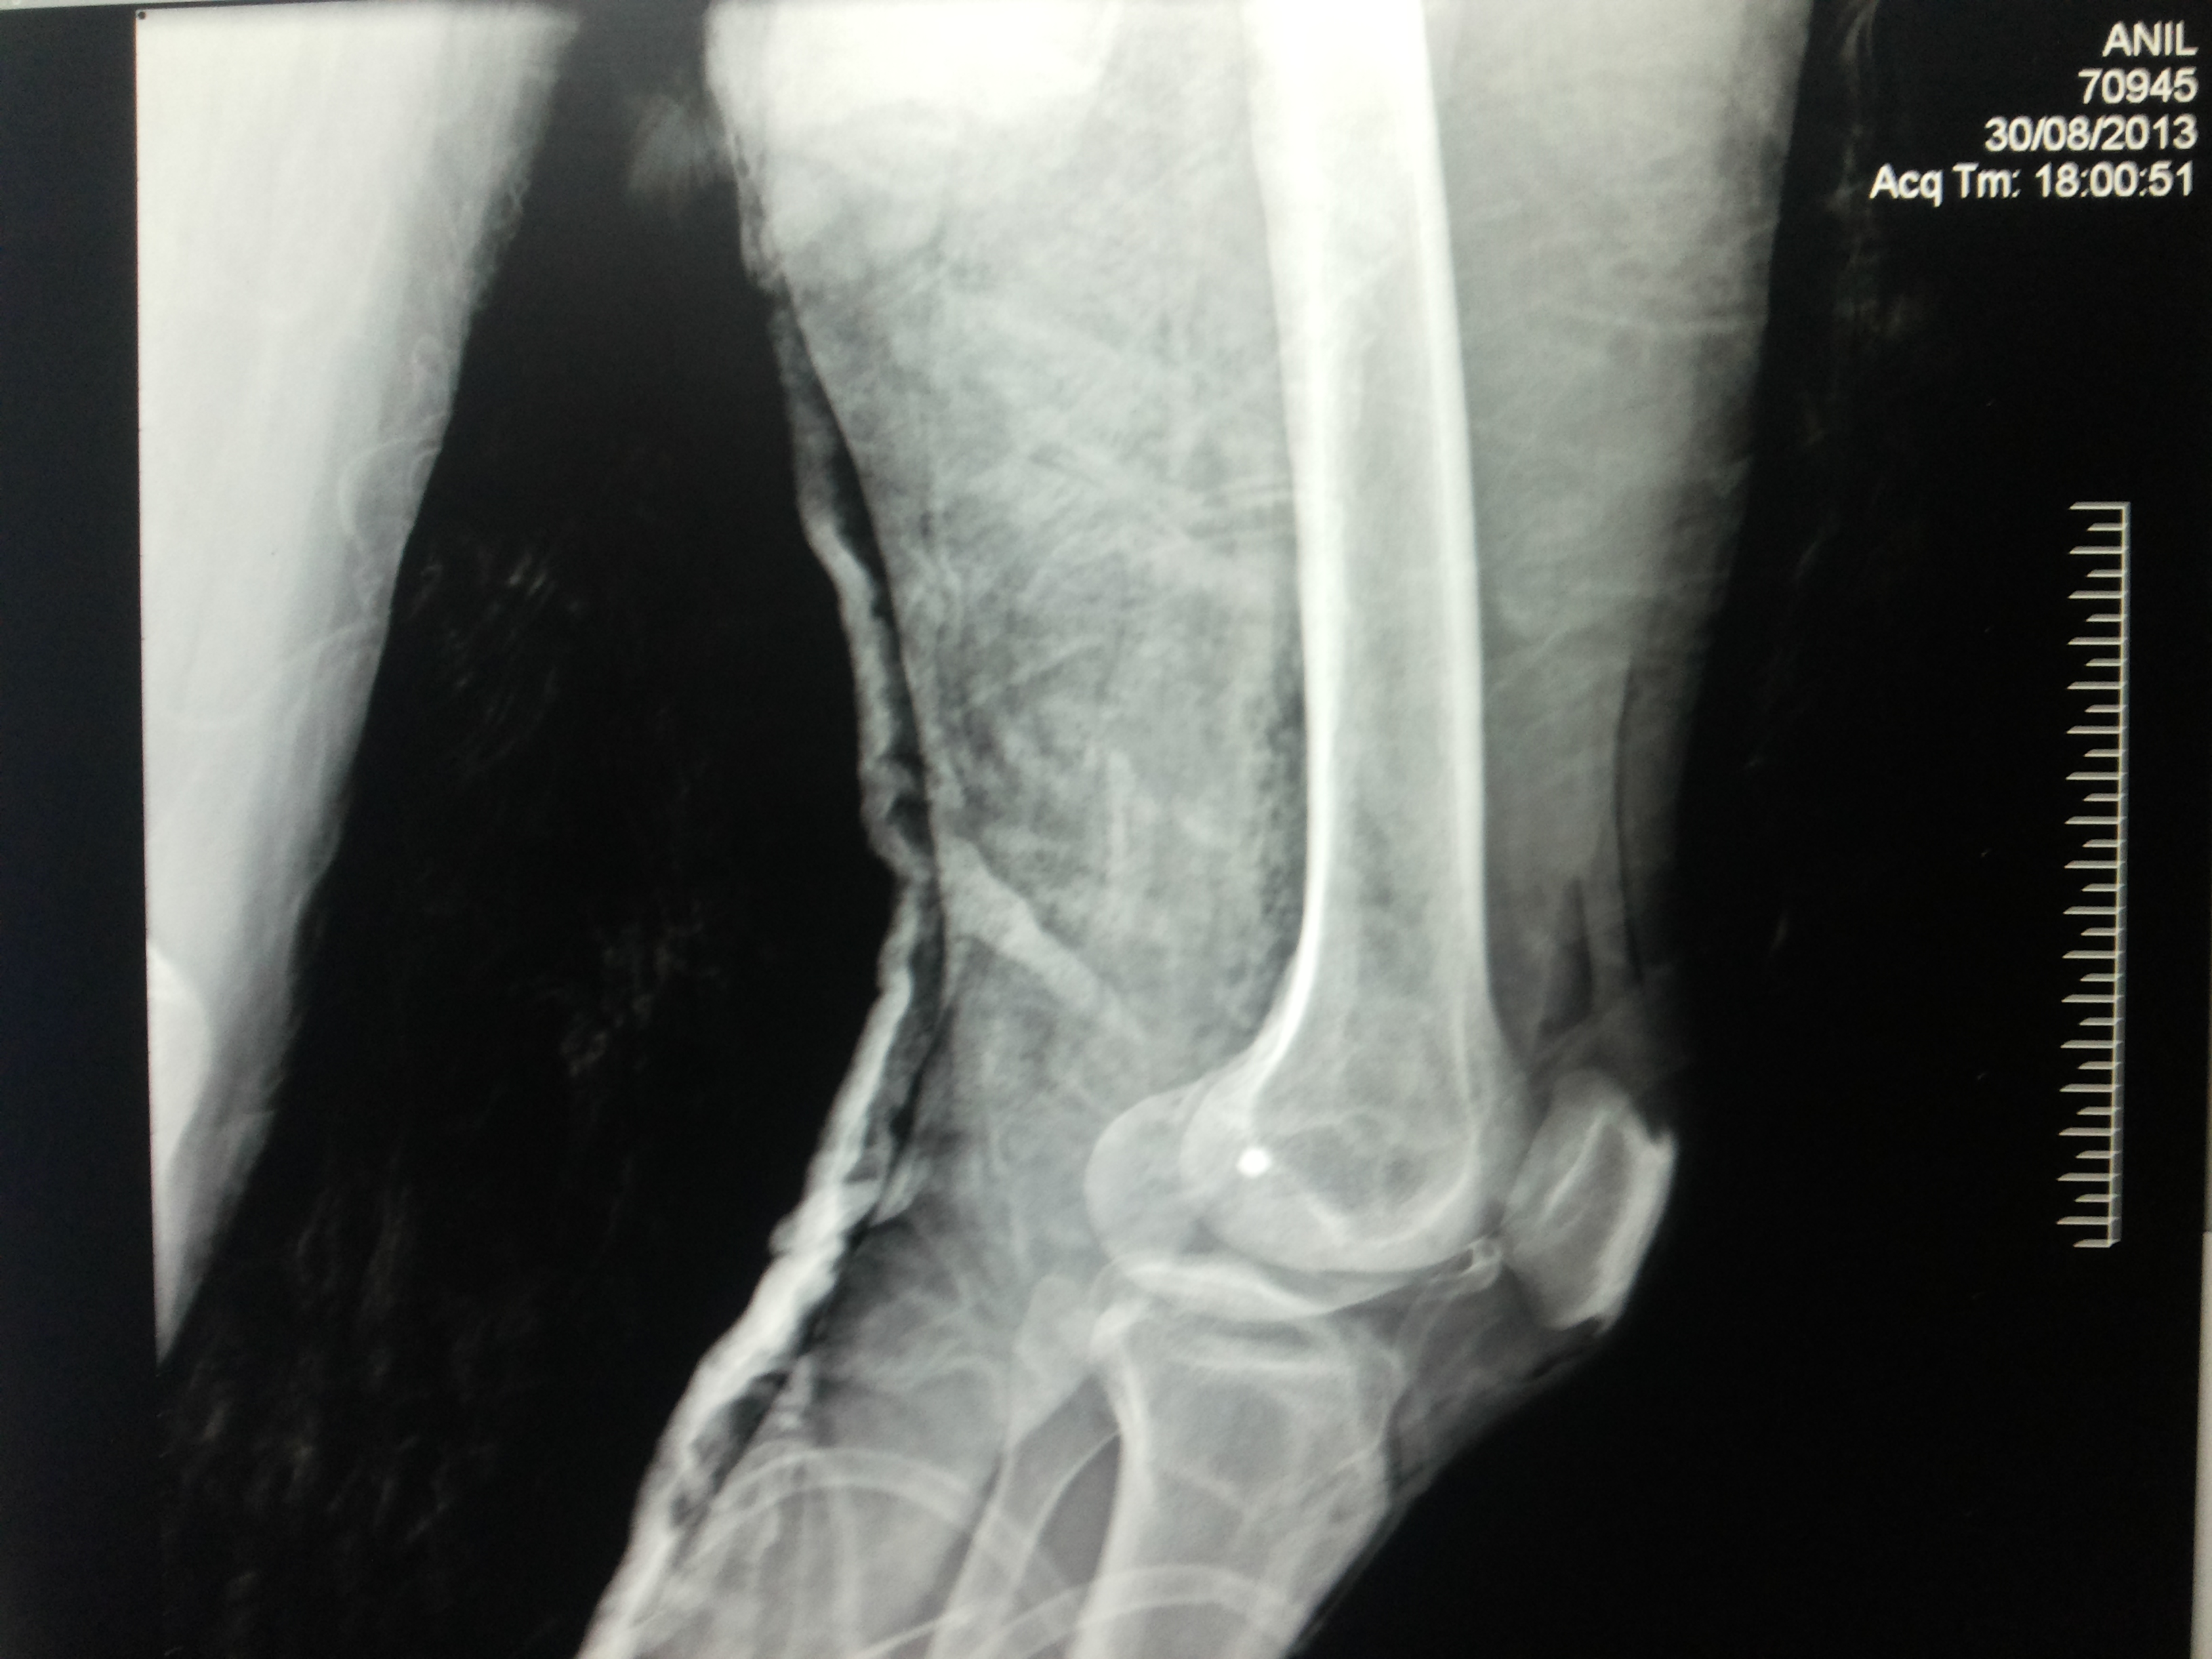

What is multi-ligament knee Injury?

Multiple ligament knee injuries happen when more than one of the knee’s ligaments is torn. They are less common than single ligament injuries.

What causes Multi-Ligament Knee Injury?

Multiple ligament knee injuries can occur during sports activities or through high-energy trauma, such as a fall from height or a car accident.

How Multi-ligament knee Injury diagnosed?

The most important way to initially diagnose these injuries is to review a thorough history with the patient to recall that their knee felt that it dislocated and slipped back in. It’s important to determine if this was solely their kneecap joint where there was a patellar (kneecap) dislocation or if it was the complete knee joint itself slipping out of place.

These injuries are very severe and potentially limb and life threatening. Thus, assessing for this and insuring that the patient’s knee function is intact, including both the status of the pulses to ensure that the artery is not injured as well as their sensation to ensure that there are no nerve injuries present is important.

How multi–Ligament Knee Injury Treated?

Nearly all cases of multiple ligament knee injury require surgery. The goal of surgery is to:

Restore knee stability

Regain full range of motion

Allow a return to athletic activities in the future

Before surgery, patients are prescribed physical therapy to work on regaining full motion and to decrease knee swelling. All patients wear a brace to protect the knee before surgery.